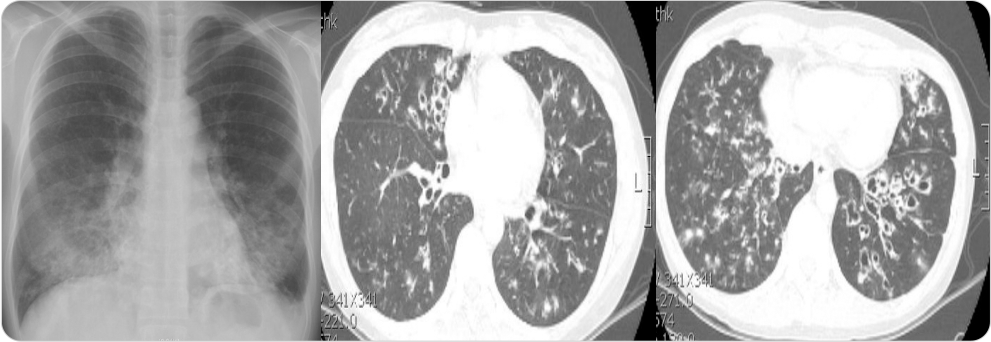

기관지확장증 진단을 위해 어떤 검사방법이 있는가요?

흉부 X선 검사 및 흉부 CT 검사에서는 폐의 침윤 소견 및 폐의 낭성 변화로 인한 기찻길 모양의 tram track sign 및

반지 모양의 signet ring sign을 확인할수 있습니다.

img

그림2 : 기관지확장증 환자의 흉부X선 (양쪽 폐중부 하부 침윤) 및 CT 사진(낭성 변화 및 tram track sign)